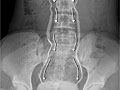

• Una pielografía intravenosa (IVP, por sus siglas en inglés) es una radiografía que muestra imágenes de las vías urinarias, incluyendo los cálculos renales.

• Una radiografía abdominal (de los riñones, de los uréteres y de la vejiga [KUB, por sus siglas en inglés]) proporciona una imagen de los riñones, de la vejiga y de los conductos que conectan los riñones con la vejiga (uréteres).